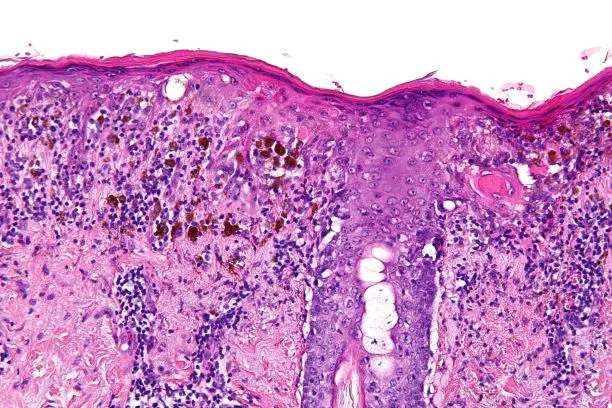

Pomyłki w badaniach histopatologicznych są poważnym problemem, który może prowadzić do błędnych diagnoz oraz niepotrzebnych interwencji medycznych. Wiele z tych błędów wynika z niewłaściwej interpretacji wyników oraz problemów z jakością próbek. Zrozumienie najczęstszych pomyłek jest kluczowe dla poprawy jakości badań histopatologicznych.

- Błędy w interpretacji wyników: Niewłaściwe odczytanie wyników badań może prowadzić do błędnych diagnoz. Często wynika to z braku doświadczenia specjalisty lub niewłaściwego przygotowania próbek.

- Problemy z jakością próbek: Niska jakość próbek, np. ich zanieczyszczenie lub niewłaściwe przechowywanie, może znacząco wpłynąć na wyniki badań.

Błędy w interpretacji wyników badań histopatologicznych mogą mieć katastrofalne skutki dla pacjentów. Często zdarza się, że specjaliści nieprawidłowo identyfikują komórki nowotworowe, co może prowadzić do opóźnienia w leczeniu. Na przykład, w przypadku pacjentki Anny Kowalskiej, błędna diagnoza raka piersi spowodowała, że straciła cenny czas na skuteczne leczenie.

Technologia odgrywa coraz większą rolę w diagnostyce histopatologicznej. Wykorzystanie zaawansowanych systemów informatycznych oraz automatyzacji procesów laboratoryjnych może znacząco wpłynąć na zmniejszenie błędów diagnostycznych. Przykładowo, zastosowanie sztucznej inteligencji do analizy obrazów histopatologicznych pozwala na szybsze i dokładniejsze wykrywanie nieprawidłowości.